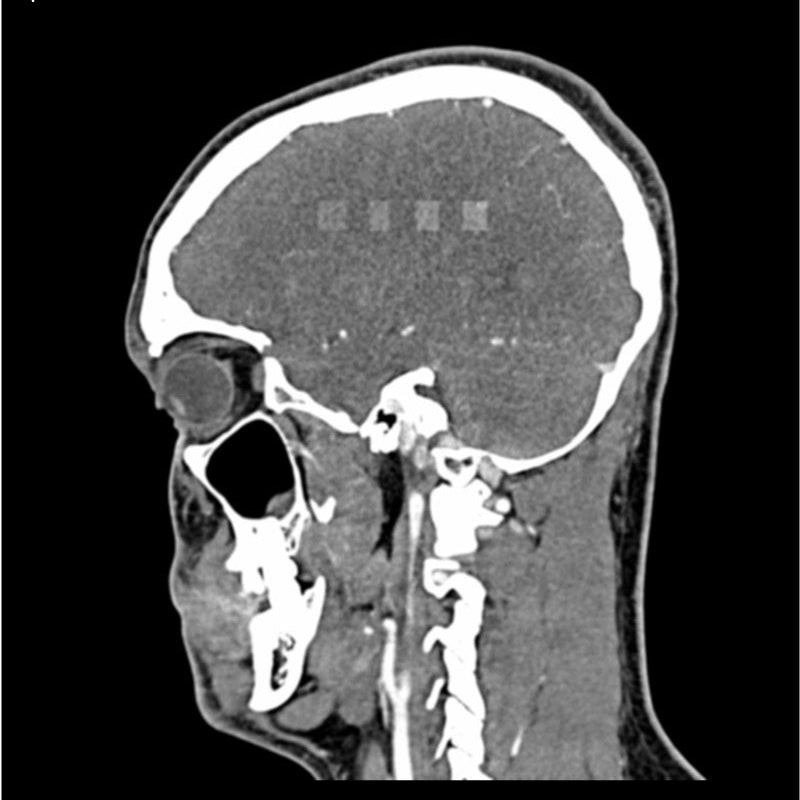

This phantom simulates a contrast medium enhanced head in arterial phase (CT angiography). It covers the vertex to the fifth cervical vertebra. The phantom has 10 low-contrast lesions in the centrum semiovale and the right hemisphere has an arteriovenous malformation.

The phantom can be used in CT (including CBCT) to evaluate and optimize imaging performance and AI-enabled diagnosis. It is also suited for training purposes. The phantom provides a detailed and realistic simulation of vascular structures, soft and bone tissue. Air voids are filled with a cellulose-polymer composite of approx. -160 HU.